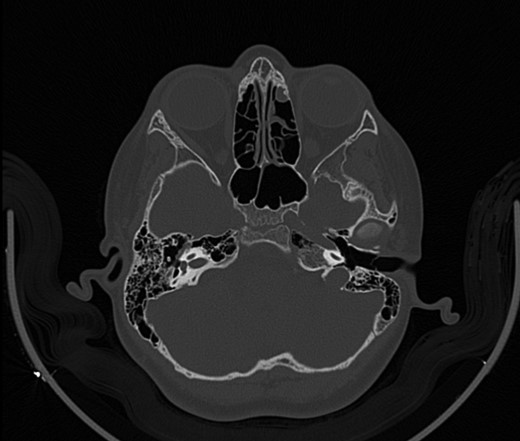

A 14-year-old male patient presented to the ENT clinic with bilateral hearing loss with no other otolaryngological symptoms. History from the patient stated a road traffic accident (RTA) 12 months ago. Meanwhile, the patient had no hearing problems prior to the RTA. Furthermore, detailed history of the accident revealed that the patient had no apparent skull injuries while pure tone audiometry (PTA) on presentation revealed bilateral conductive hearing loss and auditory brainstem response revealed right mild hearing loss and left moderate hearing loss. As a result, he was fitted with hearing aid for four months after presentation and was not compliant to it on the long-term. The patient is a non-smoker and is medically free with normal developmental milestones and negative family history of hearing complaints. Local examination of the ear revealed intact but minimally retracted tympanic membrane bilaterally. PTA was done in 2014 revealed right mild to moderate mixed hearing loss and conductive hearing loss at low frequency (Table 1). Meanwhile, the left ear had mild to moderate sensory hearing loss at high frequency (Table 2). The speech audiogram results show equal canal volume in both ears, less tympanometry pressure on the right ear and less compliance on the right ear (Table 3). The CT showed that both ossicular chains are deranged, and bilateral abnormal ossicles with no fracture or mass (Figures 1–3).

Figure 2:

CT mastoid, deranged right side ossicular disruption.